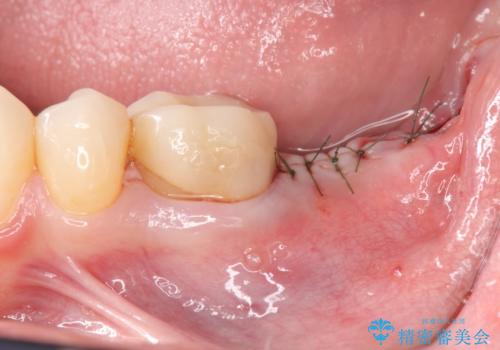

清掃性の悪いブリッジ・親知らずを除去し再根管治療・インプラントを含めた咬合再構成の計画を立てます。

- 50万円(ストローマンインプラント・骨造成・チタンカスタムアバットメント・メタルボンド×2)費用は治療当時の料金となります

掃除のしやすい環境を整えることで咬合機能・清掃性を改善することができます。